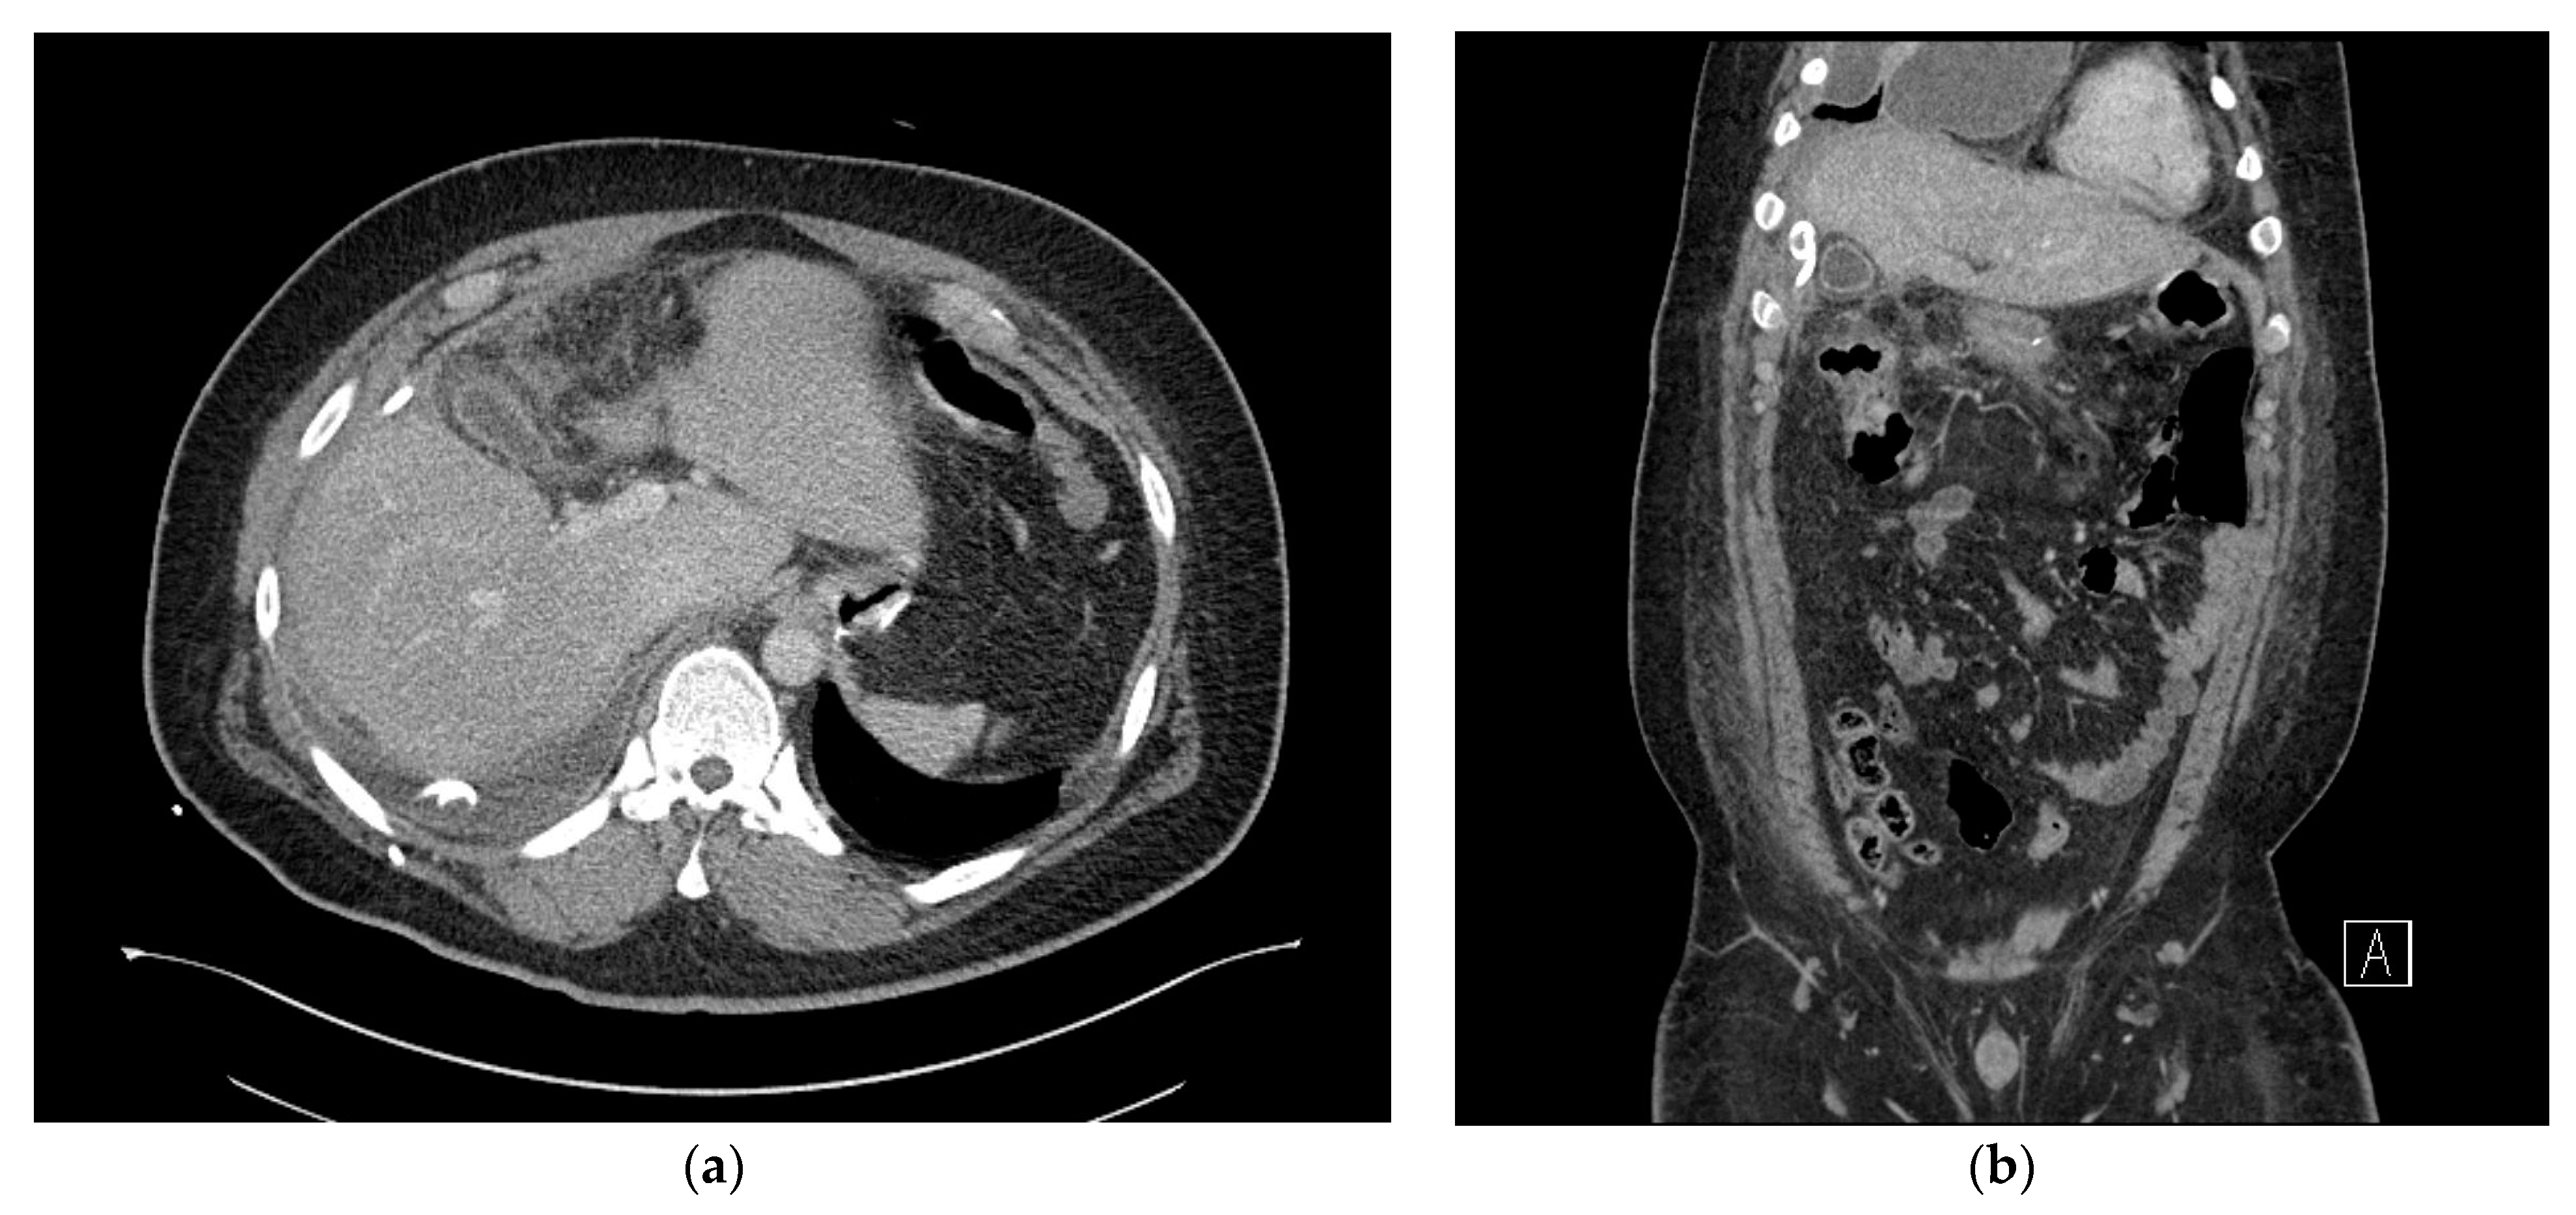

2. Case Presentation